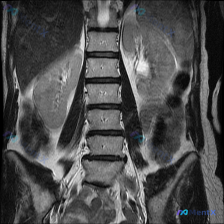

临床怀疑患者存在椎间盘病变,提供了一张T2加权冠状位磁共振影像,请读片判断是否存在椎间盘病变,拿到的影像分析结果如下:

- 双侧肾脏轮廓清晰,位置大小正常,肾周脂肪间隙清晰,无渗出模糊影

- 肾脏皮髓质分界可辨认,集合系统无扩张积水,肾门结构正常

- 双肾未见明显局灶性实性或囊性肿块,信号均匀

- 邻近结构:腰大肌对称正常,可见部分肝脾实质无异常,腰椎椎体序列整齐,未见明显骨质破坏或占位

- 结论:本层面未见明显肾脏占位或尿路梗阻迹象,单张影像信息有限,建议结合完整序列判断

针对椎间盘病变的核心问题,目前从这份报告里能得到的直接结论是:这份报告评估的是肾脏区域,未描述任何椎间盘突出、膨出、变性或神经根受压的表现,本图像未发现支持椎间盘病变的影像学证据。